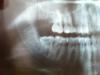

Atamax Опубликовано 28 июня, 2013 Автор Поделиться Опубликовано 28 июня, 2013 Снимок до. Ссылка на комментарий